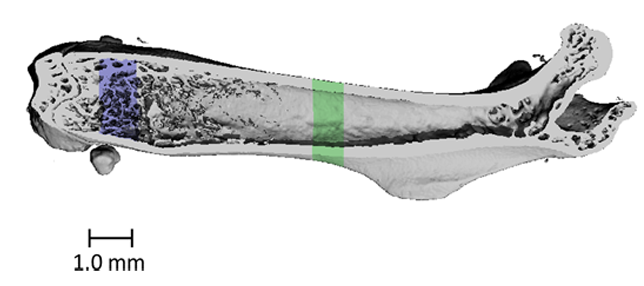

X-ray microscopy (XRM) is a nearly identical imaging modality that combines X-ray imaging with microscope technology to enhance the spatial resolution to 0.7 μm. This unique set-up allows for ex-vivo and nonorganic samples of almost any size or shape to be imaged.

The Micro-Computed Tomography Imaging Core Facility at BU has one μCT scanner and one X-ray microscope. The μCT scanner is a Scanco μCT40 system which is density calibrated on a weekly basis to keep our scans accurate. The XRM is the Zeiss Xradia Versa 520. We have multiple software options that allow for the identification of sub-regions for image segmentation, registration, and quantitative analysis. Analyses can be performed on three-dimensional regions of interest to quantify porosity, thickness, and other features of the microstructure. Additionally, two-dimensional regions of interest can be analyzed to quantify bone area, bone area fraction, cross-section area, and moment of inertia. We have the ability to render and export images in a variety of file formats.